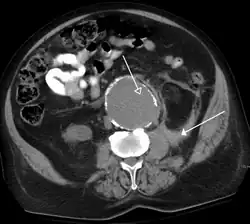

Detection and characterization of renal parenchymal masses is a frequent indication for CT. An initial noncontrast CT is important for detecting calcium or fat in a lesion, and to provide baseline attenuation of any renal masses. Following noncontrast scanning, intravenous contrast is injected and a corticomedullary phase is obtained at approximately 70 seconds (figure 7a, 7b). The corticomedullary phase is characterized by enhancement of the renal cortex as well as the renal vasculature. This phase is valuable in the evaluation of benign renal variants, lymphadenopathy and vasculature, however certain medullary renal masses may not be visible during this phase due to minimal enhancement of the medulla and collecting system. The parenchymal phase is obtained approximately 100–200 seconds after the injection of contrast material (figure 7c). Parenchymal phase imaging demonstrates continued enhancement of the cortex, enhancement of the medulla, and various levels of contrast material in the collecting system. The parenchymal phase is highly important for the detection and characterization of renal masses, parenchymal abnormalities, and the renal collecting system. This method of imaging does not evaluate for abnormalities of the collecting system.

FIGURE 7. Selected images from a renal mass specific protocol CT. Corticomedullary phase (axial 7a) demonstrates peripheral enhancement of the renal cortex with minimal opacification of the renal medulla. There is a large renal cell carcinoma in the left kidney (right in image) which can be differentiated from the normal renal parenchyma by the heterogeneous and differential enhancement. The renal artery and vein are opacified in this phase as well. The collecting system is not opacified (coronal reformat 7b). In the parenchymal phase, the renal cortex and the medulla are enhancing. The renal cell carcinoma in the left kidney is not as well defined when compared to the corticomedullary phase images, but is actually slightly more conspicuous. There is some contrast noted within the collecting system during this phase (7c).